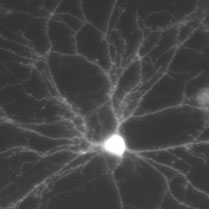

At Eötvös Lóránd University we investigate activity-dependent forms of synaptic plasticity and homeostatic regulation of intrinsic excitability of mouse hippocampal neurons.